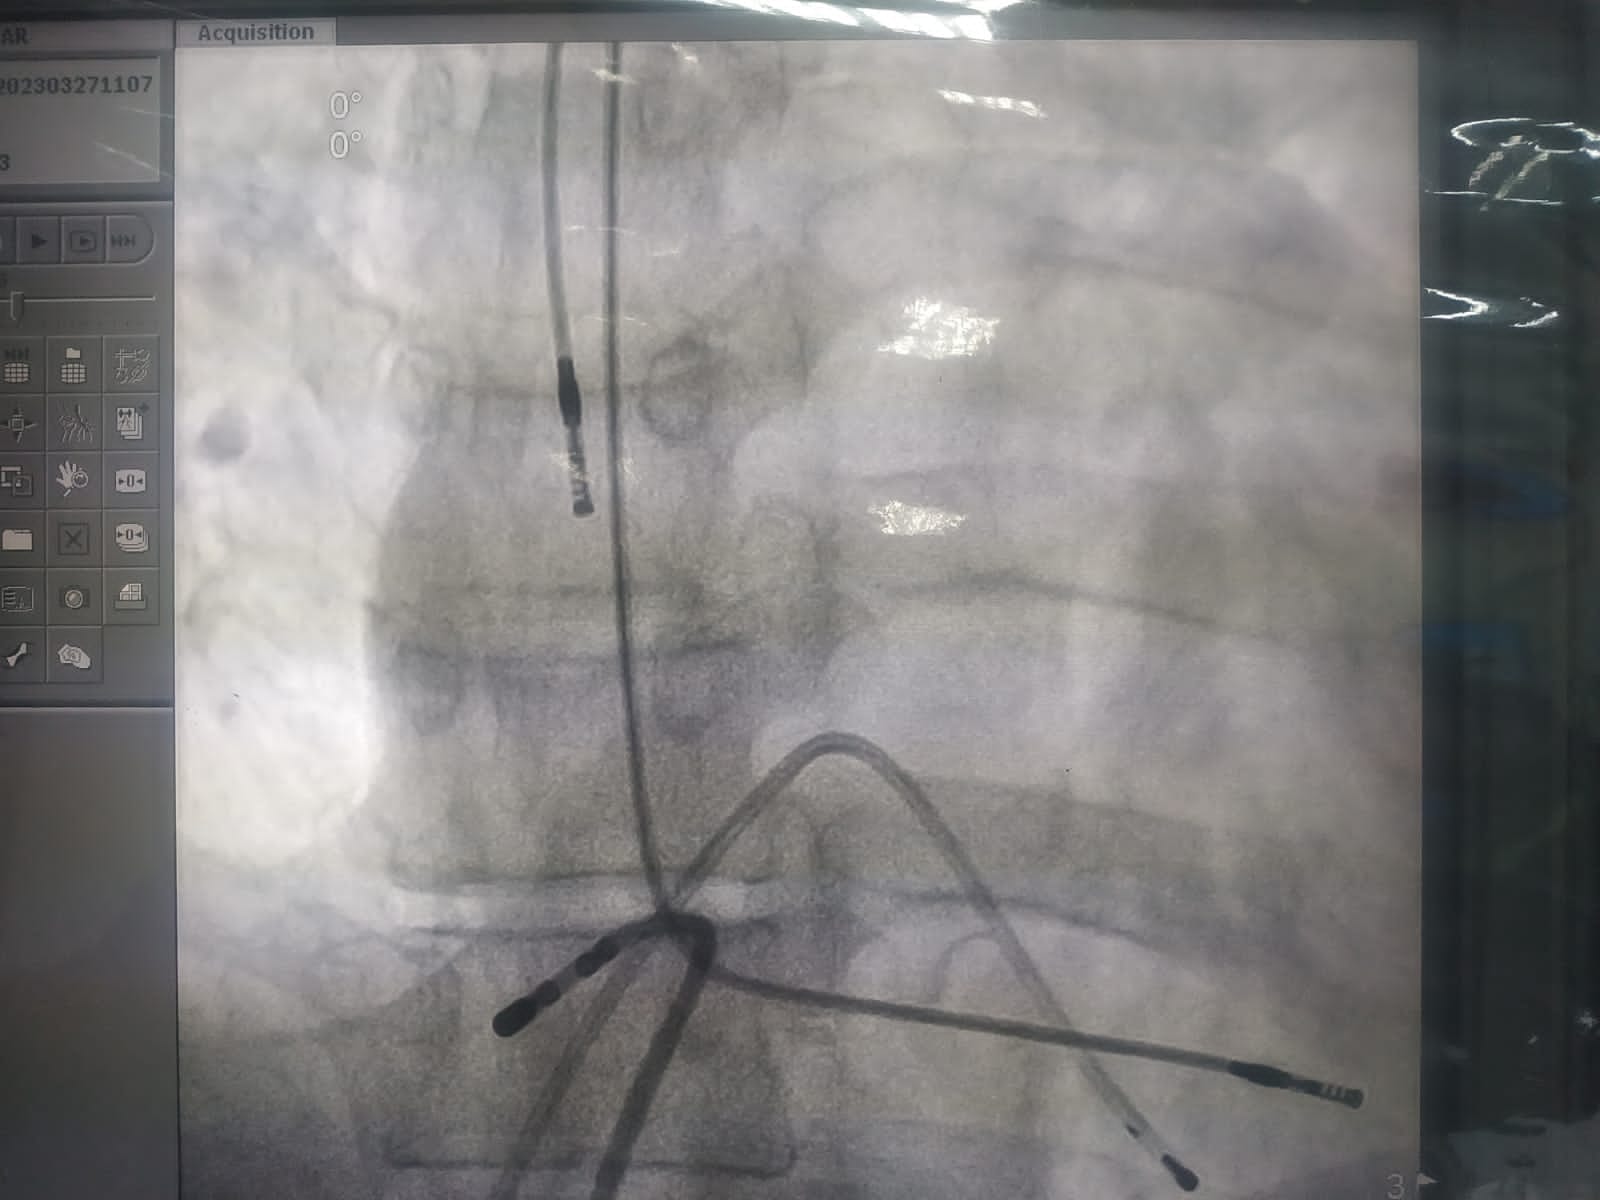

وقد أجرى فريق طبي بمستشفى القلب الجامعي عملية انتزاع منظم لضربات القلب مزروع من ٩ أعوام وذو ثلاث اسلاك لمريض يبلغ من العمر ٦٠ عاما، كما أجرى عملية أخرى لمنظم ثنائي الحجرات لمريضة تبلغ من العمر ٢٩ عاما من محافظة قنا مزروع من ٦ أعوام عن طريق الوريد كبديل لجراحة القلب المفتوح، جاءت العملية، تحت رعاية الأستاذ الدكتور أحمد المنشاوي رئيس جامعة أسيوط ، والأستاذ الدكتور علاء عطية عميد كلية الطب ورئيس مجلس إدارة المستشفيات، والأستاذ الدكتور إيهاب فوزي المدير التنفيذي للمستشفيات، والأستاذ الدكتور عصام عبد الله مدير مستشفى القلب، والأستاذ الدكتور عمرو يوسف رئيس قسم القلب، وبإشراف الأستاذ الدكتور دعاء فؤاد أستاذ أمراض القلب، و الأستاذ الدكتور صلاح عطا أستاذ أمراض القلب.

وتعد هذه العملية علاج لمضاعفات معقدة لمنظمات القلب الكهربية التي تتطلب انتزاع هذه الأجهزة، وأنها تغني عن الحاجة لجراحة القلب المفتوح، ومراكز معدودة على مستوى الجمهورية من لهم القدرة على معالجة مثل هذه الحالات، وهي تحتاج مهارات خاصة وتجرى لأول مرة في أسيوط.